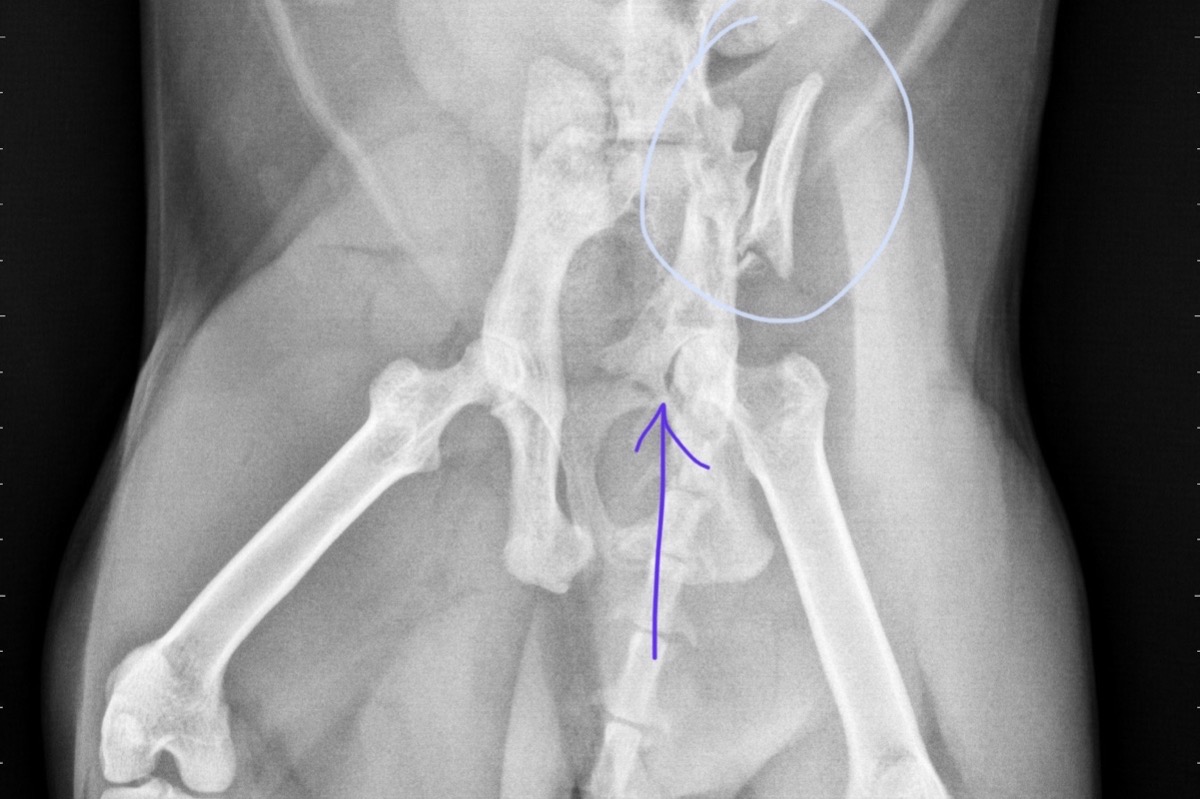

Hello friends. I am writing this with true vulnerability (something i am no good at being) because I am desperate. On Wednesday morning, I woke up and found my baby boy Bam Bam laying in the hallway unable to move. At 2:30 am the previous night, he was running around and playing when I went to bed. I have no clue what happened. No clue how. But immediately I tried getting him up and his back end slipped under him and he had no control of his legs. Carson (our son) was starting his virtual learning right then so I had dad take Bam to the emergency room immediately. After hundreds of dollars for tests etc. they called me to tell me his pelvic bone is broken in the top left area and his joint was displaced and also has possible sciatic nerve damage. He was seen by an orthopedic surgeon at the emergency room, and they quoted me for the surgery. $8,500 is the cost to get a plate put on to reconnect the pelvic bone, to put a screw into his displaced joint, and for the ct scans needed to properly treat the sciatic nerve problems. At this time I can not afford this surgery. I’ve tried every possible idea I can think of for an alternative. I was debating taking him to Mexico for the surgery. But i talked myself out of that one after reading horror stories about people taking their animals there. I’ve called 30+ places all over Southern Cali and Arizona and the cheapest place I’ve been able to contact was a place in Arizona who quoted me $1500 less than here. I am afraid to transport him in the car for that long. He is in so much pain, even with the pain meds he is on. My boy Bam is the most outgoing, social, strong, loving, and happy cat you could ever meet. He always wants to be around people. He is a purebred Bengal, who just turned 2 years old last month. He is young. He has 15 years of life left to live. The break is bad, I will attach a photo of the x-rays so you can see the break. It’s not something that will heal correctly on his own without compromising his ability to walk. Any and all donations will be greatly appreciated. I know the power of the people who love and support Kelly, Carson, and I is stronger than anything. I am asking for help because it’s time sensitive to get it done before cartilage starts to form. Thank you to every single person who pushed me to start this GoFundMe. When this happened two days ago, I refused to ask for help and I was dedicated to finding a solution on my own. But I’m at my wits end. I’m emotionally exhausted. I feel hopeless. And I don’t know how else to help him. Thank you for taking the time to read my story. And thank you in advanced for any and all donations. Bam is a special boy. If you know him, you know this. ❤️